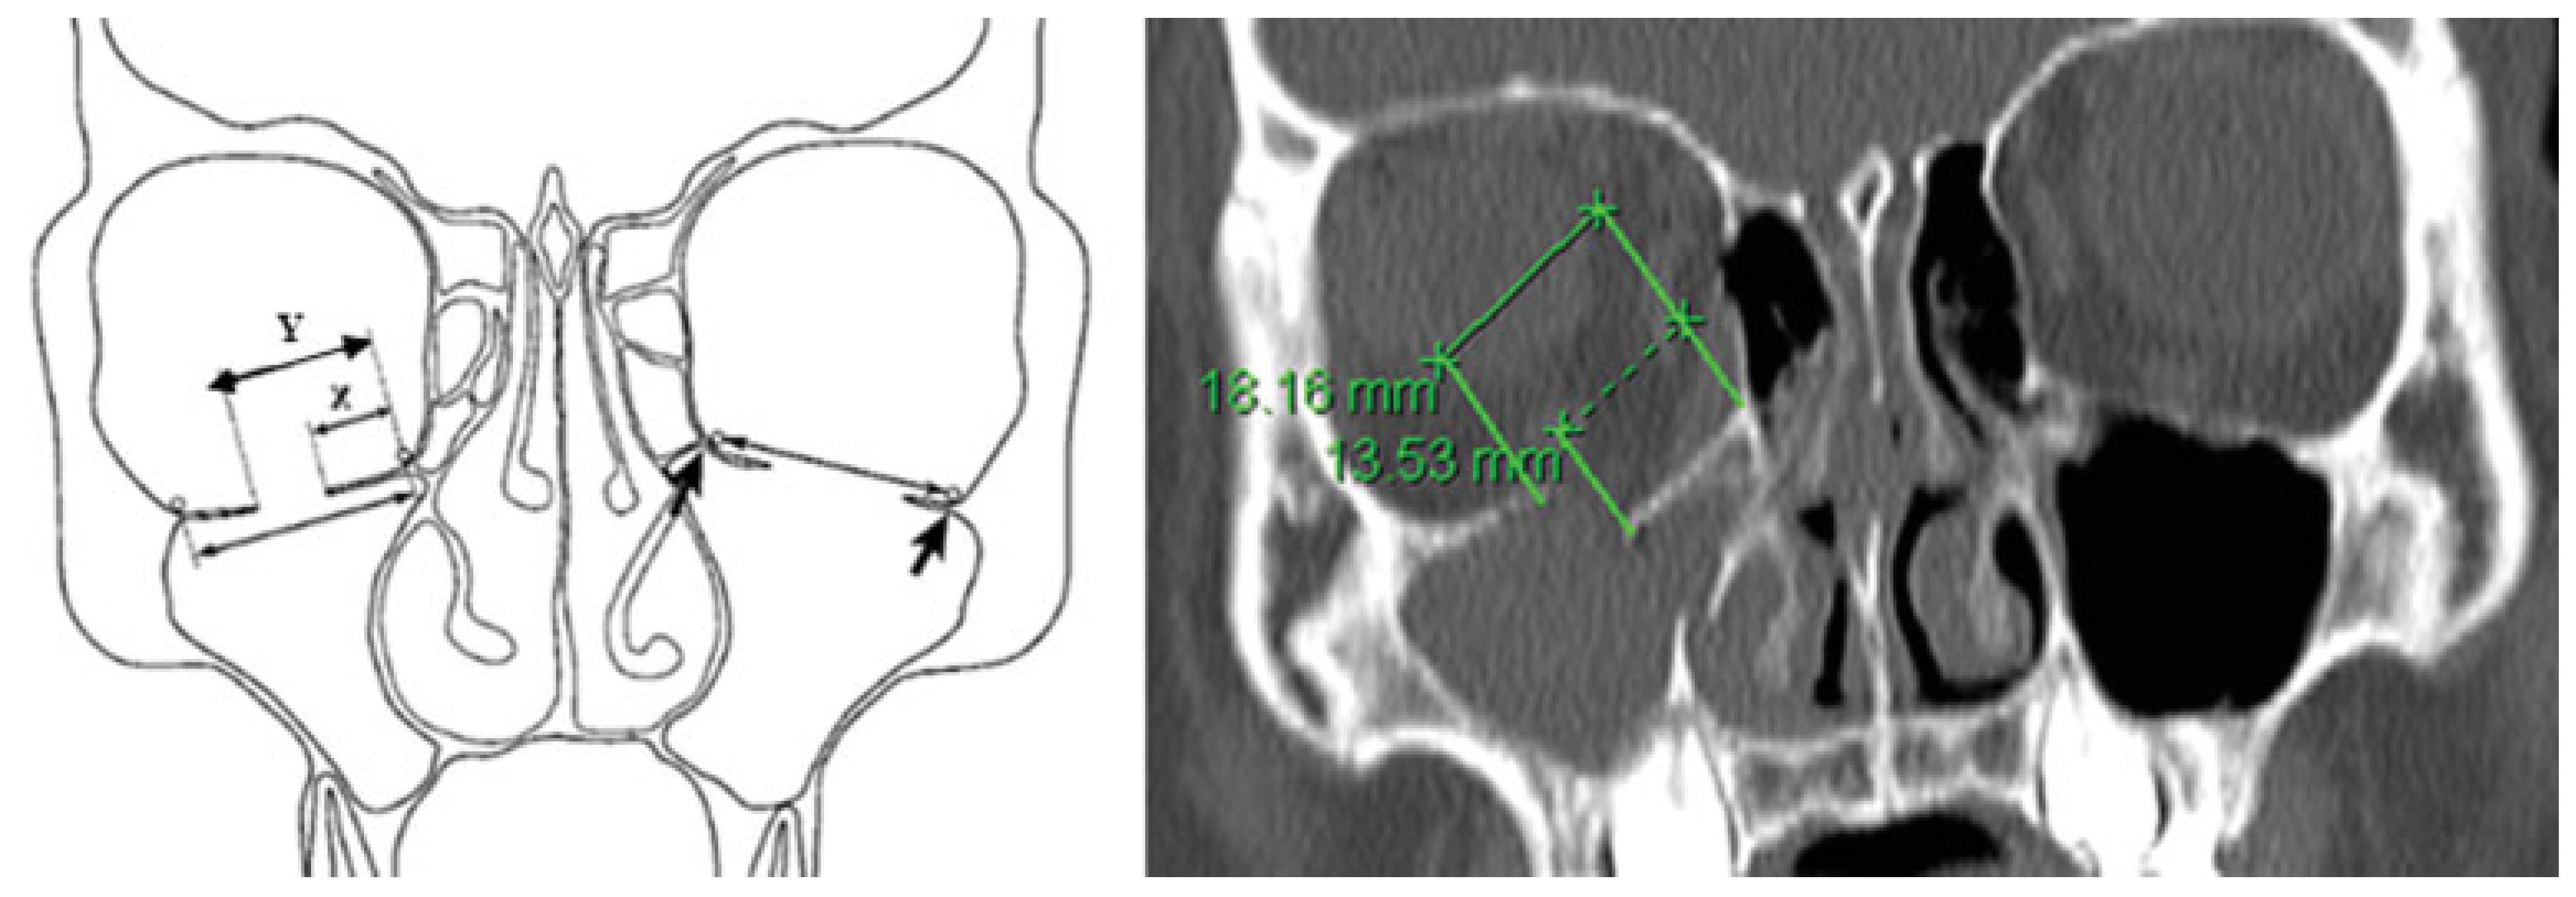

| Fracture | ||

|---|---|---|

| CT Slice | X (mm) | Y (mm) |

| 15 | 0 | 0 |

| 16 | 8.1 | 12.3 |

| 17 | 9.3 | 13.1 |

| 18 | 13.5 | 18.2 |

| 19 | 7.6 | 14.8 |

| 20 | 3.1 | 11.8 |

| 21 | 0.2 | 9.6 |

| 22 | 0 | 4.5 |

| 23 | 0 | 2.0 |

| 24 | 0 | 0 |